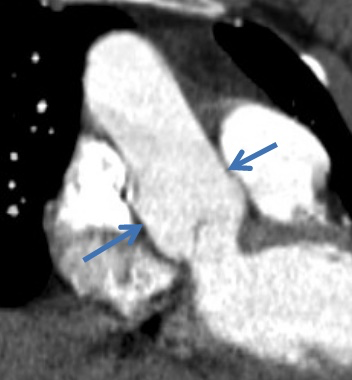

Sténose Mitrale

- Associé virtuellement toujours à un RAA (Rhumatisme Articulaire Aigu = Complication d’Angine à Streptocoques chez les enfants

- Dilatation de l’OG

- Hypertension Pulmonaire